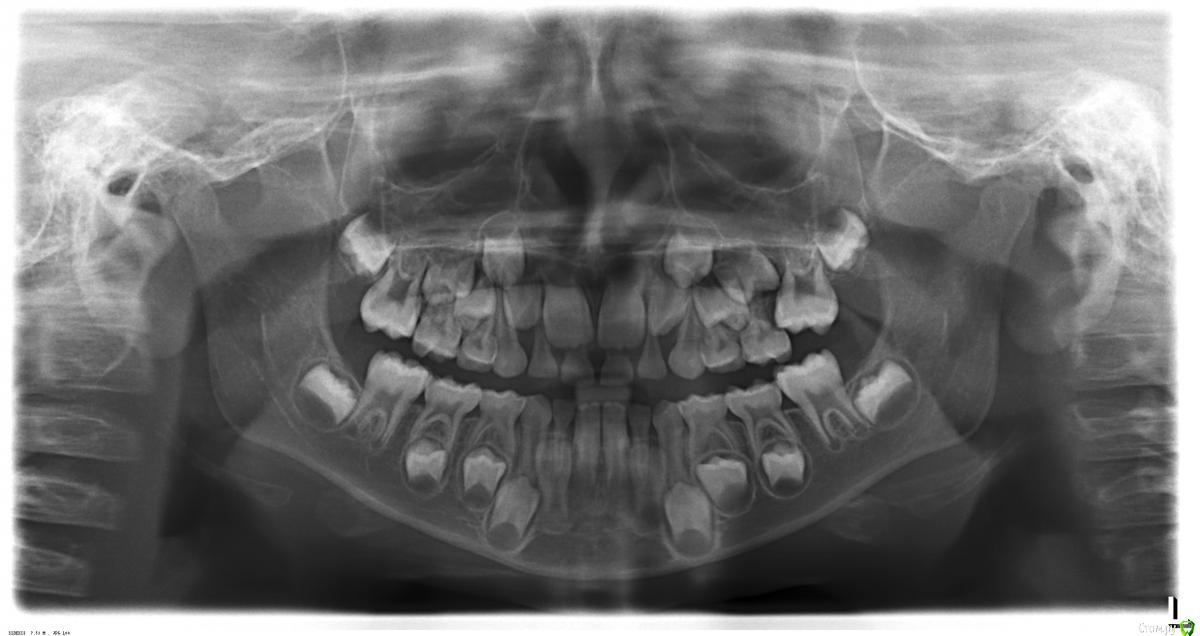

natashadmt Опубликовано 27 апреля, 2016 Поделиться Опубликовано 27 апреля, 2016 Добрый день.Очень нужен совет специалиста, чтобы принять верное решение (мальчик 7 лет)Неудачно растет 6й коренной зуб - выталкивает молочную 5ку (если смотреть на снимок, то речь идет о зоне сверху справа). Ребенок периодически жаловался на дискомфорт, но не очень активно. Сегодня воспалилась десна в зоне 5-6го зубов. Стоматолог прочистила карман, предполагает, что либо была травма десны между зубами (хотя момент травмы ребенок вспомнить не смог) либо дело в расположении зубов. Завтра прием у ортодонта, посоветуйте, пожалуйста, что делать в нашем случае? 1) Удалять ли здоровую молочную 5ку? Можно и нужно ли пытаться ее сохранять и как? Также буду очень благодарна за комментарии по ситуации в общем. Ссылка на комментарий

natashadmt Опубликовано 27 апреля, 2016 Автор Поделиться Опубликовано 27 апреля, 2016 вы же из Москвы! какие майские)) Moscow never sleeps!))) Вот именно never sleeps)))) А очень хочетсяА можете сказать, исходя из снимка, много сыну светит ортодонтических проблем? Внизу передним зубам уже мало места, они еле-еле разместились и то криво, места мало. Сверху по снимку на мой взгляд тоже все не "очень". Вопрос в том, насколько серьезно именно в нашем случае нужно подойти к поиску специалиста, много работы предстоит? Мы можем поездку и отменить, если есть риск. Что можете посоветовать? Ссылка на комментарий

natashadmt Опубликовано 28 апреля, 2016 Автор Поделиться Опубликовано 28 апреля, 2016 Спасибо за советы. Сегодня были у доступного врача, он может предложить:1) по верхней челюсти: только вариант удаления 5го и установки пластины с 2мя винтами (расширяющий и выравнивающий зуб). Сказал, что корень 5го уже почти рассосался. Если шлифовать, то под винт места не будет и выровнять 6й все равно не удастся.2) по нижней челюсти расширяющую пластину с одним винтом Можете пояснить, как можно выровнять рост 6ки при сохранении 5го зуба? В чем плюсы минусы предложенного плана? Прикладываю еще несколько фото зубов. Ссылка на комментарий